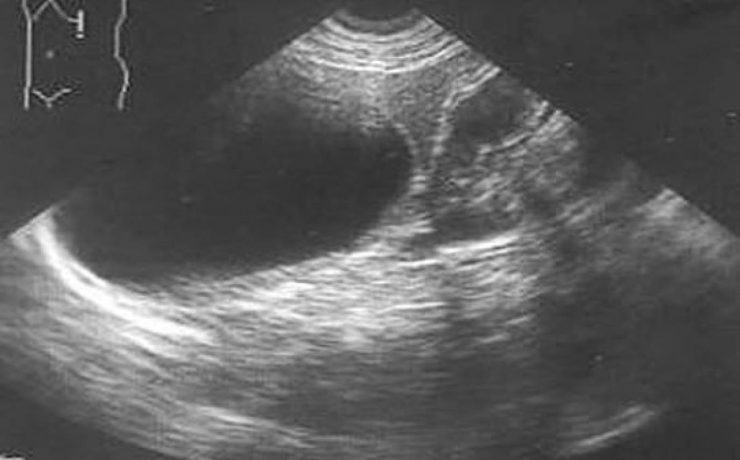

Quiste hidatídico primario de bazo

La hidatidosis es una enfermedad causada por Equinococus granulosus y que afecta principalmente a zonas endémicas donde existe disminución de la higiene, lugares con corrales o animales con problemas intestinales, alimentos donde se consumen vísceras crudos, en lugares urbanos se ha visto este tipo de patología donde abundan los perros